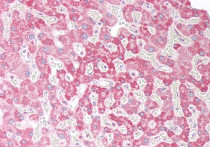

ARG64115 anti-ORP5 antibody IHC-P image

Immunohistochemistry: Paraffin-embedded Human kidney tissue. Antigen Retrieval: Steam tissue section in Citrate buffer (pH 6.0). The tissue section was stained with ARG64115 anti-ORP5 antibody at 5 µg/ml dilution followed by AP-staining.